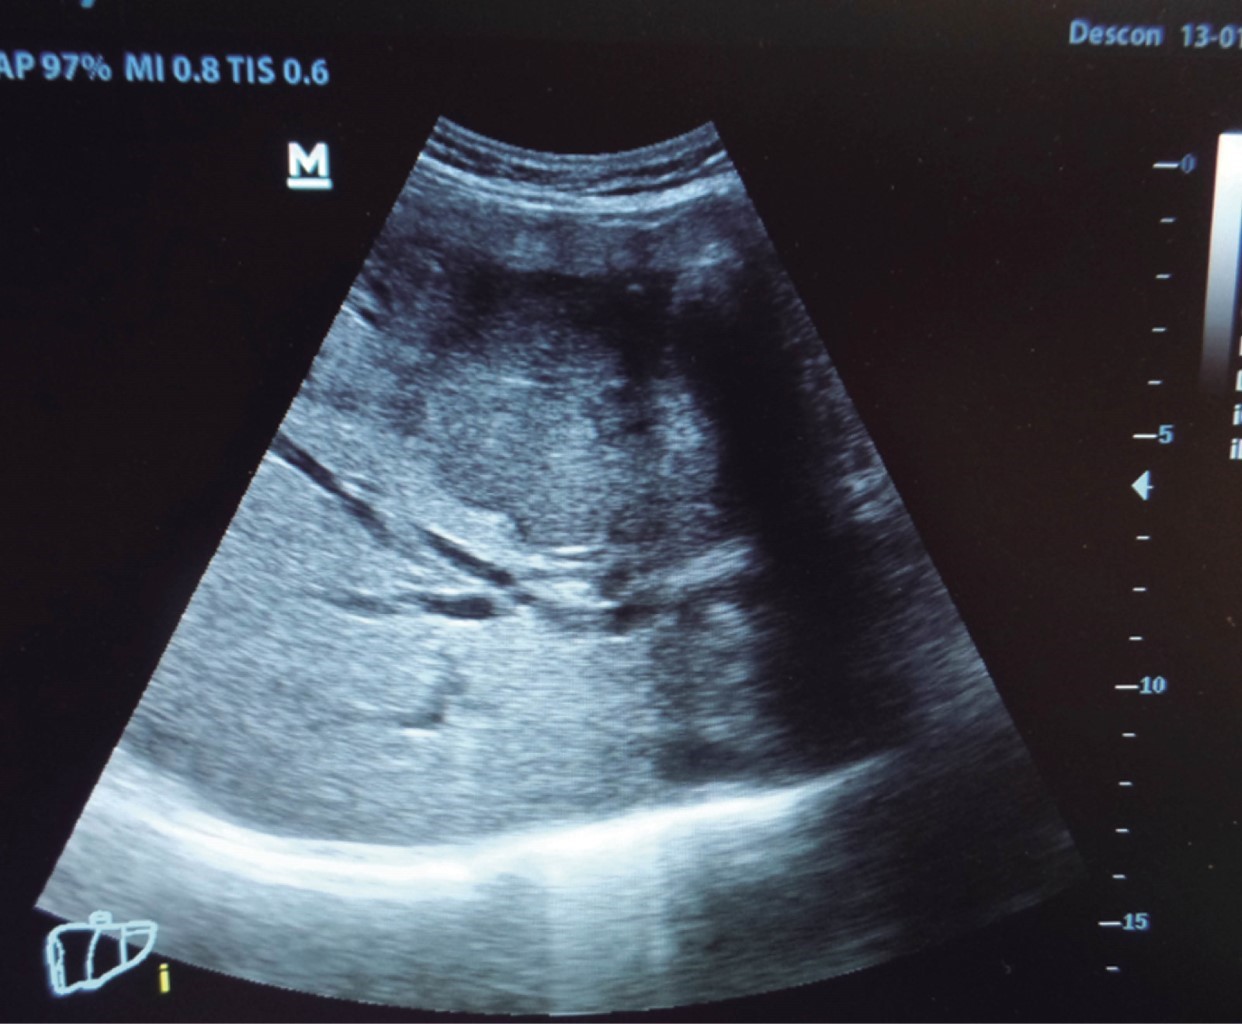

The general surgeon deals with clinical problems involving the digestive tract, the neck, the abdominal wall, and disorders of the circulatory system and the thorax. A paper published in 2008 by Lindelius,15 demonstrated that the implementation of ultrasound by the general surgeon in cases of acute abdominal pain increased diagnostic accuracy by 7.9%. In the daily consultation of the specialty, incorporating sonographic scanning to the explored area adds minutes to the clinical examination that provides data of notable value due to its objectivity and precision. The abdomen is usually the site most frequently explored by general surgeons. It is possible in a daily consultation to do the entire upper abdominal ultrasound protocol in minutes, which includes both upper quadrants and the flanks, being able to observe the liver, gallbladder and bile ducts, both kidneys, the spleen, part of the pancreas and, with the help of color Doppler, the main vessels of the region such as the inferior vena cava, abdominal aorta, portal vein, splenic vessels, and the hepatic artery. There may be limiting factors such as gastric contents, the filling level of the gallbladder, or the patient's constitution and ability to cooperate with the study. However, with daily practice, sufficient skills and refinement are acquired to achieve, with accumulated experience, images of immediate diagnostic relevance. In the training phase, contrasting our findings with information available on the web, with imaging colleagues, or surgeons already experienced in ultrasound, will allow the essential feedback and mentoring of any learning curve. Traditionally, it was considered that those organs containing a mixture of liquid and gas (intestine, stomach) are not assessable by ultrasound; the gas produces a rarefaction effect, as it does not compress the waves as a solid tissue or a liquid medium, the signals are then scattered preventing them from returning as echoes and allowing the processor to form an image congruent with the scanned organ. However, when this condition changes due to a pathological state, it is possible to identify the intestinal or gastric contents and give us a more approximate idea of what is happening in that abdomen. We can, for example, tell whether a stomach is full of liquid or whether the intestine contains solid, liquid, or gaseous residue. Today's equipment can even see the intestinal wall in detail when it is dilated. It can be distinguished when the colon is fluid-occupied at the level of the left flank as might be in amebic colitis or intestinal occlusion,16 where dilatation of the small bowel ≥ 25 mm, abnormal peristalsis, the presence of free intraperitoneal fluid and edema of the bowel wall are seen (Figure 2). In cases of acute abdominal pain, ultrasound can immediately allow differential diagnoses, such as the finding of a pyelocaliceal dilatation due to nephrolithiasis (Figure 3) or an abdominal aortic aneurysm (Figure 4). A prospective study performed in Irvine, California,17 found that the diagnostic ability of the first contact physician performing ultrasound to detect cholelithiasis has a specificity of 87% and a sensitivity of 82%, while the ultrasonography test performed by an imaging physician had a sensitivity of 83% and a specificity of 86%. In other words, by saving the patient's time, the diagnosis of cholelithiasis is feasible by adding a few minutes to the initial physical examination. In cases of appendicitis, the diagnostic method considered the gold standard is computed tomography (CT). However, it has drawbacks, such as its availability, its cost, and the risk of radiation in children and pregnant patients. In such situations, especially in children, females, or thin patients, ultrasound is a powerful tool that complements the initial clinical examination. The advantages of ultrasound over CT are its ubiquity (it is already in the emergency room), low cost, absence of radiation, and differential diagnosis with gynecologic or genitourinary causes of pain. In appendicitis, the sensitivity and specificity of CT are 99.4% and 80.0%, respectively. For ultrasound, the diagnostic sensitivity is 83% and specificity is 90%. The rate of negative appendectomy is slightly higher in the CT group than in the ultrasound group, i.e., 7.1% (3/42) (CT) compared to 4.67% (5/107) (ultrasound). It should be emphasized that ultrasound is an operator-dependent technique. Experience and quality of the equipment play an important role.18 Appendicitis has several characteristic findings, such as an edematous wall and general thickening. A noncompressible non-peristaltic tubular structure measuring more than 6 mm in diameter in the right lower quadrant is taken for criteria of positivity (Figure 5).19-21

INCIDENTAL FINDINGS ON ROUTINE ABDOMINAL EXAMINATION

An incidental finding is any undetermined phenomenon detected during an examination that is not directly related to the symptom that prompted the examination. However, it may have clinical relevance, suggesting further examination or consultation.22 It is for the general surgeon, accustomed to seeing patients with digestive complaints, to encounter the overwhelmingly common "abdominal distention". "It's my colitis, doctor", patients say. From time to time, we have found surprises of vital transcendence such as renal tumors, an intravesical nodulation that turned out to be a transitional cell carcinoma (Figure 6), or liver metastases (Figure 7), aneurysms of the abdominal aorta,23,24 or thrombosis of the femoral vein, among others. The most frequent incidental finding in our practice is fatty liver,25 which can be the trigger for an early diagnosis of a metabolic syndrome and facilitate examinations and relevant clinical guidance for timely intervention in this endemic disorder. Simple, hepatic, or renal cysts are common. In such cases, their diameter is measured, and the absence of heterogeneous content or blood flow inside (Doppler) is confirmed, especially in renal cysts, that they do not replace the normal renal parenchyma (as in familial polycystic kidney disease). Without these characteristics, they are confirmed to the patient as simple cysts and do not merit further intervention. The hepatic parenchyma can be observed interrupted in its usual echogenicity by some abnormal phenomenon such as adenomas or hemangiomas, which have no major clinical significance; but in the presence of any hepatic nodulation, we must record the image and request an expert opinion, and send the patient to the imaging service and have it protocolized by means of ultrasound and/or contrast CT. These findings will allow further studies to confirm the diagnoses and reorient the therapeutic approach with an opportunity that a simple palpation would never have achieved. The patient will always be grateful for an examination with such objectivity.